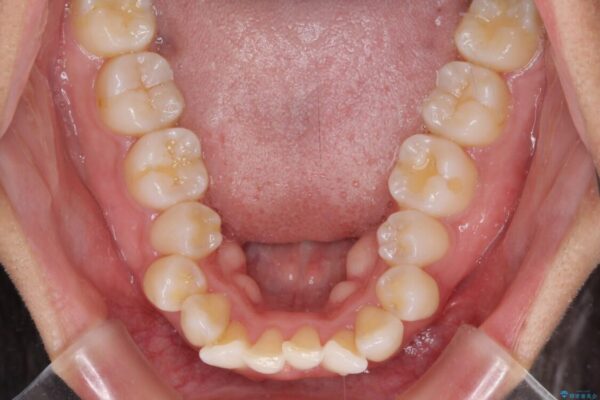

治療前

• 抜歯矯正で唇を閉じやすく 目立たないワイヤー装置 治療前画像

下唇が突き出るような口元の突出感が気になるとのことで来院された患者様です。

上下顎ともに前突した歯列であったので、上下ともに左右の第1小臼歯4本を抜歯し、ワイヤー装置にて矯正治療を行うこととしました。